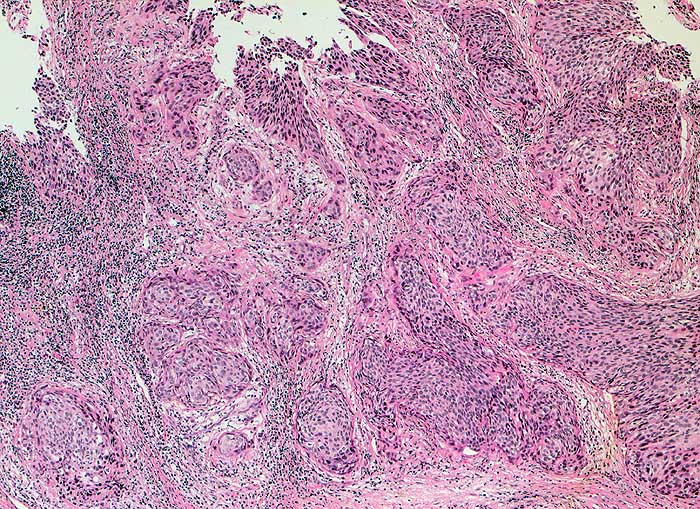

PathoPic – image database / PathoPic ID 6385 - gering verhornendes Plattenepithelkarzinom

gering verhornendes Plattenepithelkarzinom

Portio

Solide zapfenförmige Tumorinfiltrate im Stroma. Keine Verhornung.

Dauerblutung seit 2 Wochen, deutlich gefässinjizierte Ektopie, sofortige Kontaktblutung.

Histologie

25